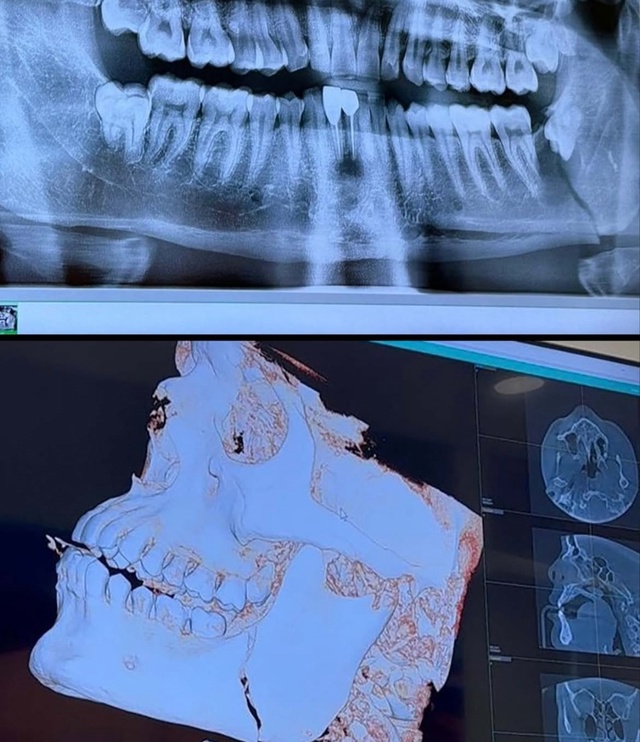

«Помню, в начале второго раунда я получил удар кроссом и подумал: “Черт, как же это было больно!”», — рассказал Мотта. «Я почувствовал, как мой зуб немного движется. Сначала я подумал, что сломал зуб. После каждого боя, завершившегося техническим нокаутом или нокаутом, мы всегда должны проходить обследование в больнице, и именно там выяснилось, что у меня два перелома челюсти».

Изначально Николас планировал вернуться в Таиланд, где он проходил свой тренировочный лагерь перед боем. Однако вместо этого ему пришлось отправиться в Лас-Вегас, чтобы проконсультироваться со специалистом по поводу своей травмы. Мотта объяснил, что стоматолог выявил кисту, вызванную зубом мудрости, которая сделала его челюсть более хрупкой, что в итоге и привело к перелому.

«Мне сделали операцию и установили титановую пластину, чтобы зафиксировать челюсть на месте», — пояснил Мотта. «Забавно, но Рафаэль Дос Аньос прислал мне рентгеновский снимок своего лица, и оно полностью усыпано титановыми пластинами. Он написал: ‘Брат, я все равно стал чемпионом после этого’».